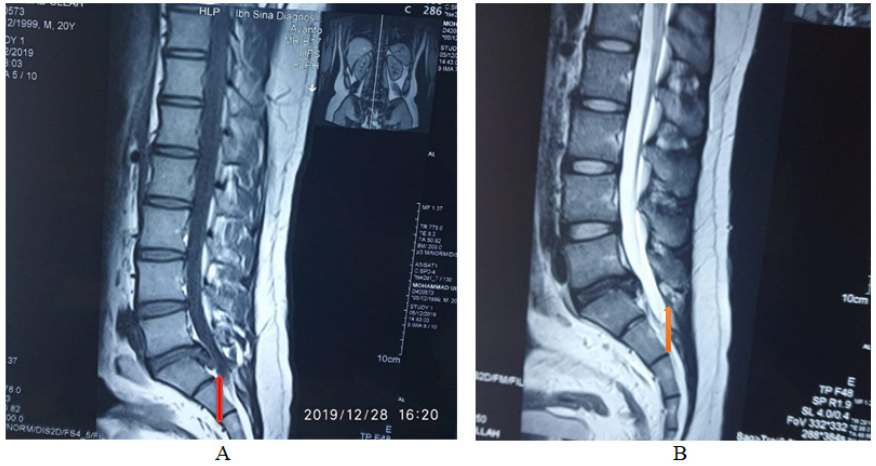

Figure 1  A–D shows mri of lumbosacral spine tiw sagittal & t2w sagittal & axial view ( key film).

Arrow on films reprsinting the venous plexus that resembling herniated disc at l5-s1 level. The venous plexus causing canal stenosis at same level (c)& mr myelogram (d) arrow showing globular hyperintensity attched with thecal sac.

As in our case, the preoperative diagnosis was presumed a case of canal stenosis due to centrally herniated disc at L5-S1 level by history, clinical examinations & radiological investigations. Patient was planned for conventional discectomy at L5/S1 level on torso flat prone position with torso on hall frame, abdomen hanging free & hip flexed. After having fenestration done, a plexus of tortuous veins was found in epidural space at L5/S1 level on right side. Nerve root on right side was pushed laterally by varices. Canal was decompressed by punching out ligamentum flavum & discectomy on left side. Postoperatively the radicular pain didn’t subsided satisfactorily hence Resection of varices was planned for second setting after having proper evaluation & investigations of venous varicosity.